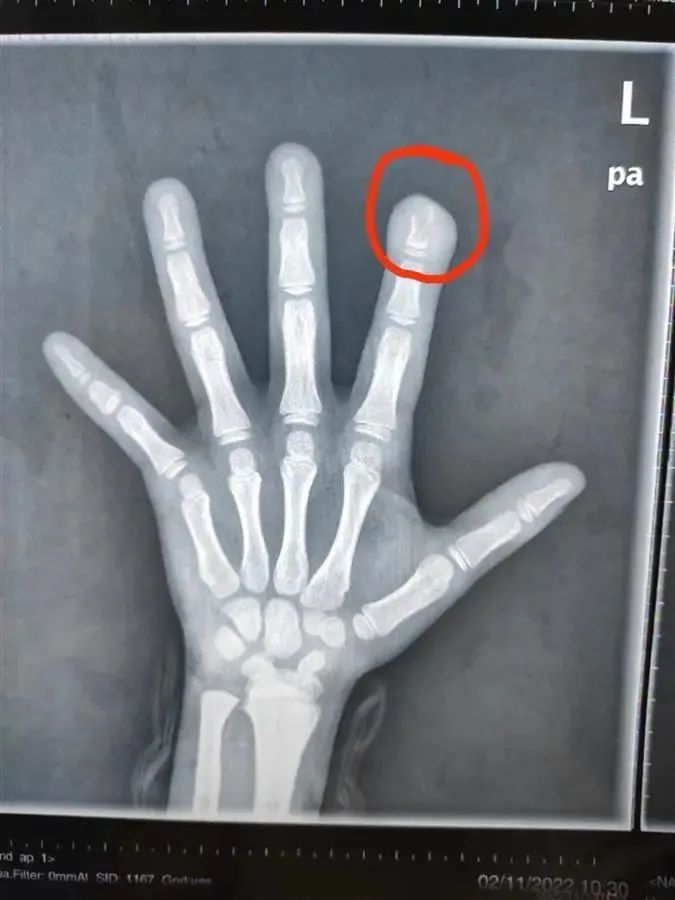

孩子左手食指指尖破潰感染

還有膿性分泌物流出

指骨遠(yuǎn)節(jié)有骨質(zhì)破壞

近1厘米長

是細(xì)菌侵蝕導(dǎo)致的

也是常說的骨髓炎

圖片

文文的食指有部分殘缺(通訊員供圖)